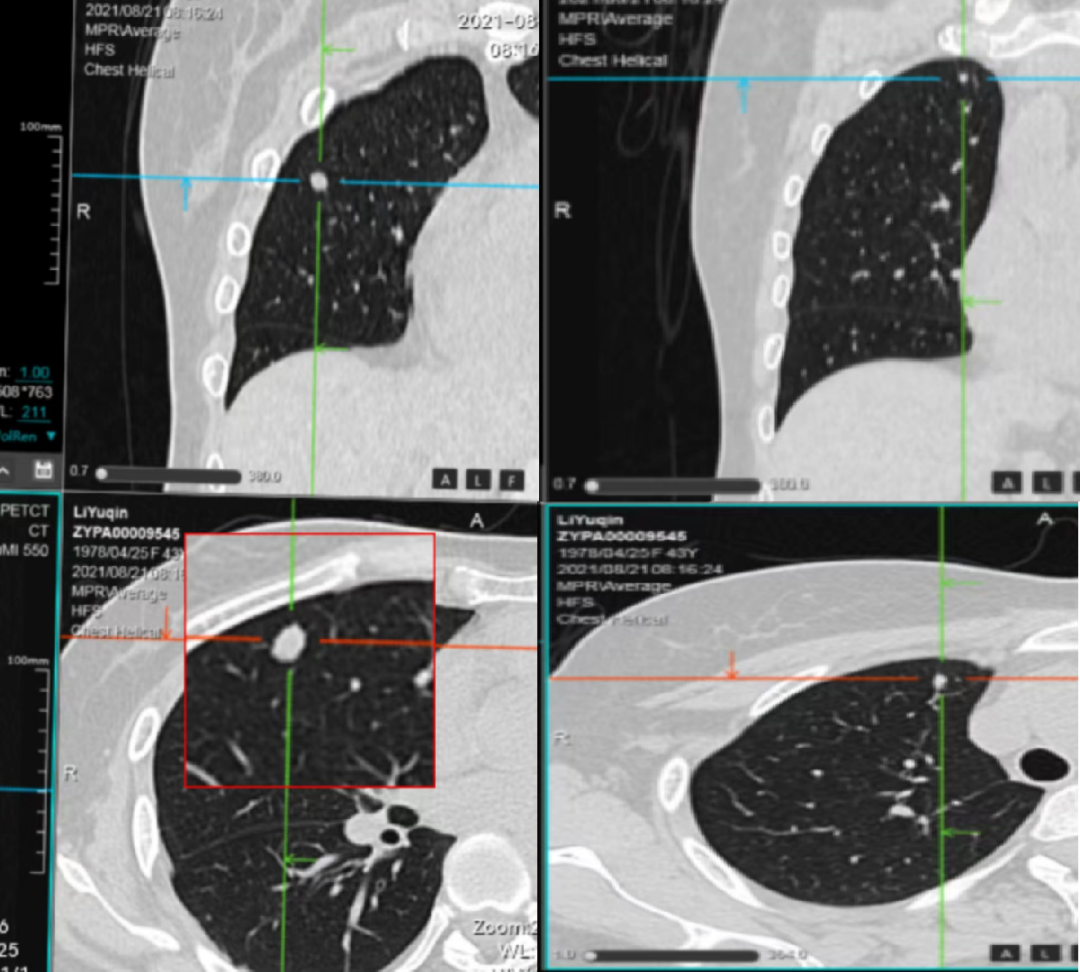

▲2021-4-12 检查项目:盆腔CT平扫(普+特)、上腹CT平扫(普+特)、胸部CT平扫(普+特)、盆腔CT强化+平扫(普+特)、上腹CT强化+平扫(普+特)和胸部CT强化+平扫(普+特)的影像表现与印象

第1次术后16个月、还纳术后11个月复查。

▲2021-5-17 检查项目:盆腔CT平扫(普+特)、上腹CT平扫(普+特)、胸部CT平扫(普+特)、盆腔CT强化+平扫(普+特)、上腹CT强化+平扫(普+特)和胸部CT强化+平扫(普+特)的影像表现与印象

第1次术后19个月、还纳术后14个月复查。

▲2021-8-12 检查项目:盆腔CT平扫(普+特)、上腹CT平扫(普+特)、胸部CT平扫(普+特)、盆腔CT强化+平扫(普+特)、上腹CT强化+平扫(普+特)和胸部CT强化+平扫(普+特)的影像表现与印象

▲2021-10-8 检查项目:胸部CT平扫(普+特)、盆腔CT强化+平扫(普+特)和胸部CT强化+平扫(普+特)的影像表现与印象

▲2021-11-25 检查项目:胸部CT平扫(普+特)、上腹CT平扫(普+特)、盆腔CT强化+平扫(普+特)、上腹CT强化+平扫(普+特)和胸部CT强化+平扫(普+特)的影像表现与诊断意见